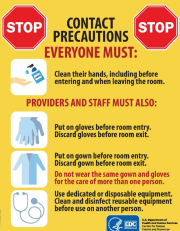

| 06:42, 15 באוגוסט 2023 | Contact Precautions poster.png (קובץ) |  |

748 קילו־בייטים | Motyk | 1 | |